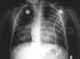

Bronchitis

Bronchitis is inflammation of the bronchi (large and medium-sized airways) in the lungs that causes coughing. Symptoms include coughing up sputum, wheezing, shortness of breath, and chest pain. [Source: Wikipedia ]